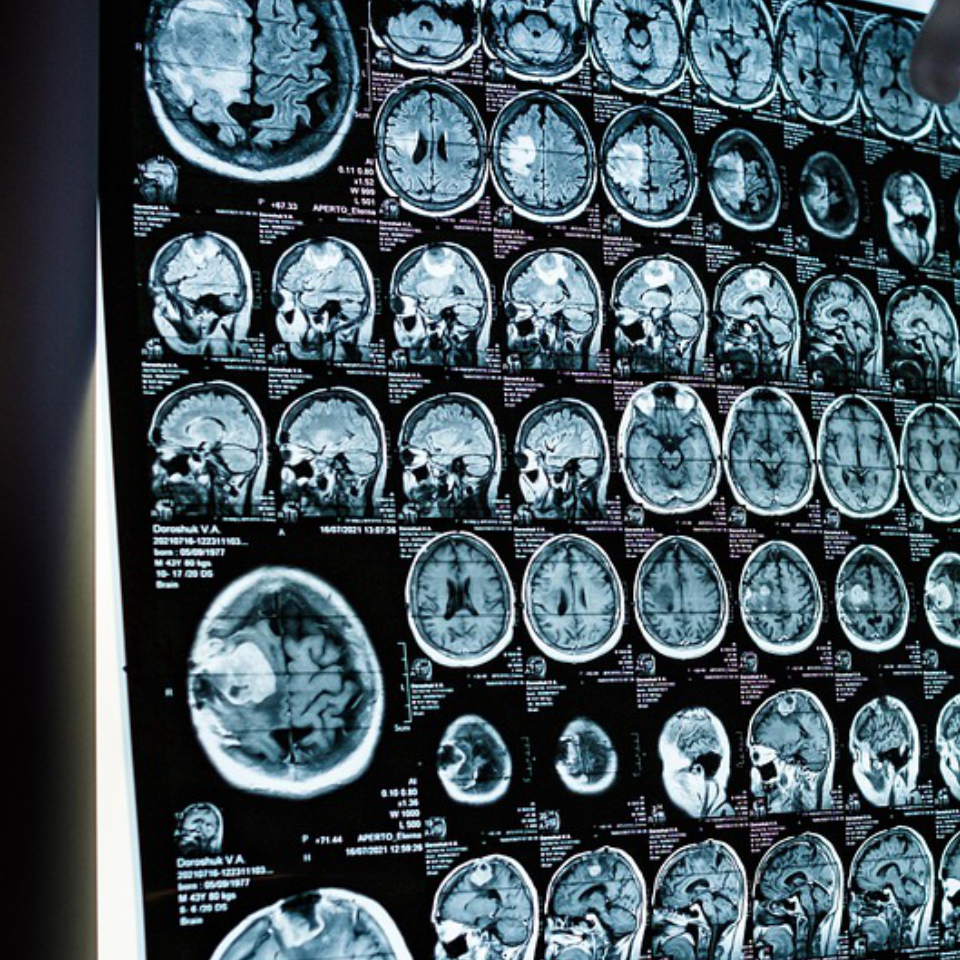

TiN Plasmonic Biosensor in Glioma Detection

Malignant gliomas are one of the most dangerous brain tumors. This application uses TiN Plasmonic biosensor for its detection.

In Vivo Liquid Biopsy for Glioblastoma

via AFM & LSPR Sensing of Exosomal CD44 / CD133. Non-invasive monitoring of glioblastoma malignancy.